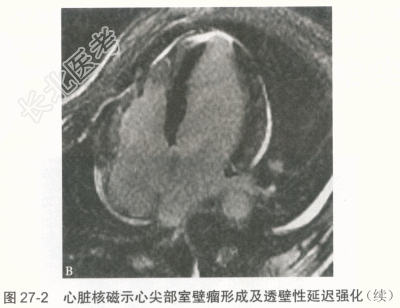

患者男性,41岁,2016年2月20日晚间无明显诱因出现发热,体温最高38.0℃,伴轻微胸闷、憋气、头晕、头痛、恶心,偶有呕吐及四肢酸痛,无胸痛及肩背部放射痛,自行服用对乙酰氨基酚1片后症状不缓解。21日晨起体温38.5℃,伴全身乏力,至当地医院行胸片检查未见明显异常,行血常规检查提示白细胞、中性粒细胞偏高(具体数值不详),考虑炎性病变,回当地诊所继续输液治疗(药名及剂量不详),效果欠佳。22日上午患者出现胸闷、憋气、四肢无力,伴恶心,无呕吐,输液期间症状反复发作,逐渐加重。23日2:00胸闷、憋气明显,突发意识丧失,急呼120送至保定市第一中心医院,检查结果示:CK-MB39.6ng/ml↑,肌红蛋白431.0ng/ml↑,肌钙蛋白18.4ng/ml↑,BNP536.00pg/ml↑,D-二聚体0.7μg/ml↑,ALT615.00U/L↑,AST781.00U/L↑,肌酐204.9μmol/L↑,当地医院诊断"重型心肌炎",给予抗炎、抗病毒治疗,静脉泵入异丙肾上腺素、多巴胺及甲泼尼龙,体温逐渐回落至正常,但胸闷、憋气、乏力等症状无缓解。当晚17:00左右送至我院急诊科,转运过程中胸闷、憋气症状进行性加重。心电图示:三度房室传导阻滞。心脏超声:左室整体功能减退,二、三尖瓣轻度反流,少量心包积液,未见节段性室壁运动障碍。我院给予异丙肾上腺素、甲泼尼龙冲击、盐酸多巴胺等治疗,给予急诊临时起搏器。随后收入我科,心电图提示加速性室性自主心律。吸烟史10余年,约20支/天,无饮酒史,家族无遗传病史。 入科后因临时起搏导管感知不良,更换临时起搏器期间患者突然出现意识丧失,伴抽搐,持续约2分钟后患者意识逐渐恢复,但躁动明显,伴呼吸困难,氧饱和度维持在85%左右,行气管插管术,吸出大量粉红色泡沫样痰,给予托拉塞米40mg静脉推注,呼吸机持续辅助呼吸,氧饱和度逐渐回升至100%。入科后查体:血压71/49mmHg,心率55次/分,双肺大量湿啰音,心音低钝,未闻及明显杂音。检查:CK-MB、肌红蛋白、肌钙蛋白、D-二聚体、ALT、AST、γ-GGT、肌酐均升高,BNP>35000pg/ml,血常规示:白细胞计数和中性粒细胞升高。2月23日肺部CT提示双侧肺水肿,双侧胸腔积液。经应用激素及其他辅助药物治疗后,患者病情逐渐稳定,临床症状及化验检查.心电图、胸部CT均明显改善。 患者3月7日复查超声心动图提示心尖部室壁瘤形成,不除外心肌梗死所致(图27-1)。因而进一步行冠脉CT及心脏磁共振。冠脉CT未见明显冠状动脉狭窄。心脏磁共振:①左室心尖节段性延迟强化并反向运动;②左侧-侧壁心肌弥漫水肿并延迟强化,明确有室壁瘤形成(图27-2)。3月7日EBV-DNA定量检测阳性,C-反应蛋白6.28mg/dl。